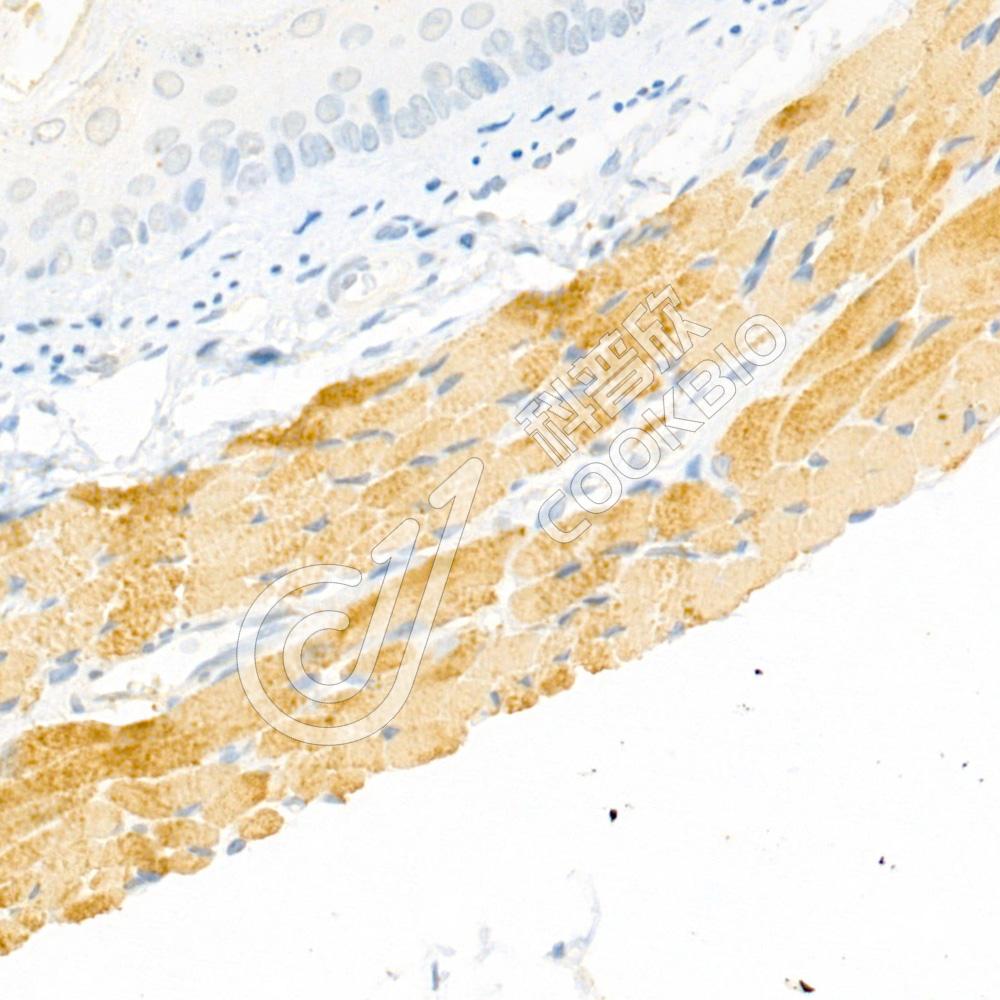

IHC检测Myosin light chain 3蛋白(货号 K1333723).

样品: 大鼠食管, 4%多聚甲醛 (货号KSG1101) 固定12-24小时.

抗原修复: 柠檬酸抗原修复液(干粉, pH 6.0) (KSG1201), 98℃, 20分钟.

—抗: 1: 2300稀释, 4℃ 孵育过夜.

二抗: S-vision免疫组化多聚二抗(山羊抗兔),即用型 (货号KB3906), 室温孵育20分钟.